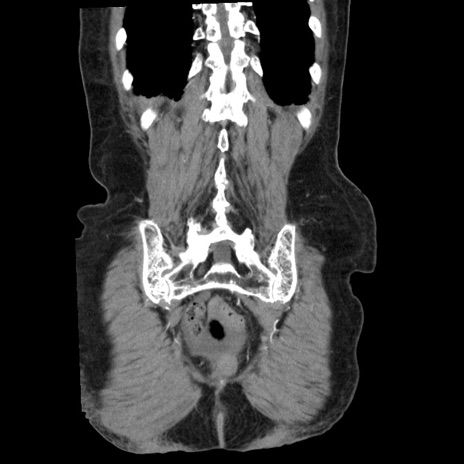

症例1(冠状断像)

【症例】80歳代女性

【主訴】腹痛

【現病歴】8時間前から腹痛あり来院。

【既往歴】糖尿病、脂質異常症、子宮体癌にて子宮全摘術

【身体所見】意識清明・会話良好だが腹痛で苦悶様、全腹部にわたって反跳痛と圧痛あり

【データ】WBC 13600、CRP 0.14、LDH 224、CK 90

矢状断像